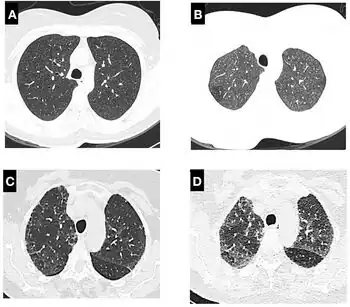

A chest X-ray or CT is necessary to differentiate between pneumonitis and pneumonia of an infectious etiology. Some degree of pulmonary fibrosis may be evident in a CT which is indicative of chronic pulmonary inflammatory processes. Diagnosis of Pneumonitis is often difficult as it depends on a high degree of clinical suspicion when evaluating a patient with a recent onset of a possible interstitial lung disease. In addition, interpreting pathologic and radiographic test results remains a challenge to clinicians. Pneumonitis is often difficult to recognize and discern from other interstitial lung diseases.[7]

- High-Resolution Computed Tomography (HRCT) consistent with pneumonitis

Clinical tests include chest radiography or (HRCT) which may show centrilobular nodular and ground-glass opacities with air-trapping in the middle and upper lobes of the lungs. Fibrosis may also be evident. Bronchoalveolar Lavage (BAL) findings coinciding with pneumonitis typically include a lymphocytosis with a low CD4:CD8 ratio.[7][12]

Reticular or linear patterns may be observed in diagnostic imaging.[7] Pneumonitis may cause subpleural honeycombing, changing the shape of the air spaces in an image, which may be used to identify the respiratory disease.[7] The interlobular septa may also thicken and indicate pneumonitis when viewed on a scan.[7]

Since pneumonitis manifests in all areas of the lungs, imaging such as chest x-rays and Computerized tomography (CT) scans are useful diagnostic tools.[3] While pneumonia is a localized infection, pneumonitis is widespread.[3] A spirometer may also be used to measure pulmonary function.